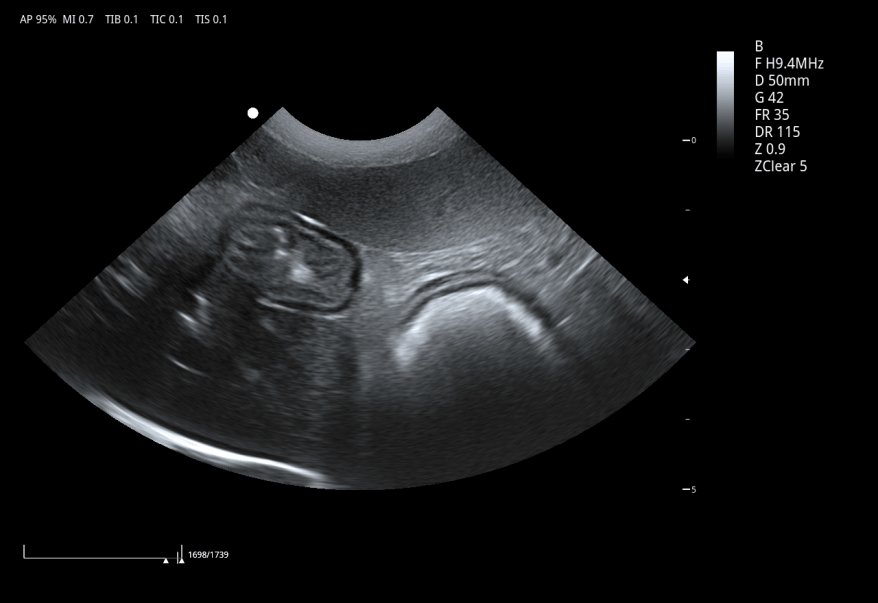

6C1PD ● 3.5-12.0MHz ● Micro convex array probe ● For Abdomen, Cardiology, Reproduction |

3C5PD ● 1.0-7.5MHz ● Convex array probe ● For Abdomen and Reproduction |